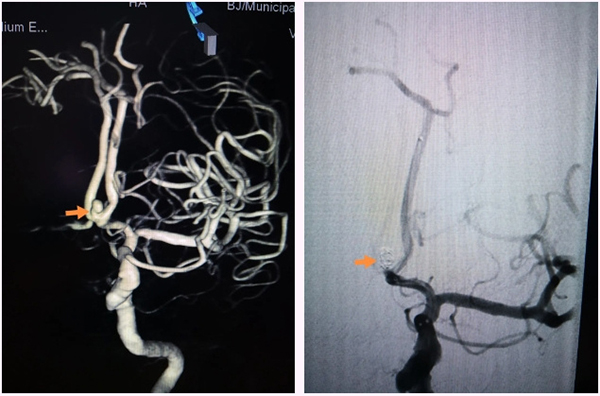

7月9日,在导管室、麻醉科的全力配合下,由神经外科脑血管病介入团队在全麻下实施了前交通动脉瘤弹簧圈栓塞术。手术中,神经外科介入团队沉稳操作,克服了严重头颈动脉粥样硬化及迂曲的困难,一步步精准操作将中间导管送达指定位置,栓塞微导管小心进入动脉瘤,栓塞弹簧圈缓慢送入动脉瘤腔内。经过2个小时的手术,患者这颗颅内“不定时炸弹”被成功拆除。过程顺利,动脉瘤达到致密栓塞,载瘤动脉通畅。术后第一天为患者实施了腰大池置管,引流血性脑脊液。术后第二天患者神志转清,拔除气管插管,目前正在进一步治疗中。患者家属由衷的表示感谢,特意写了感谢信。

▲手术前后对比:动脉瘤致密栓塞,载瘤动脉通畅